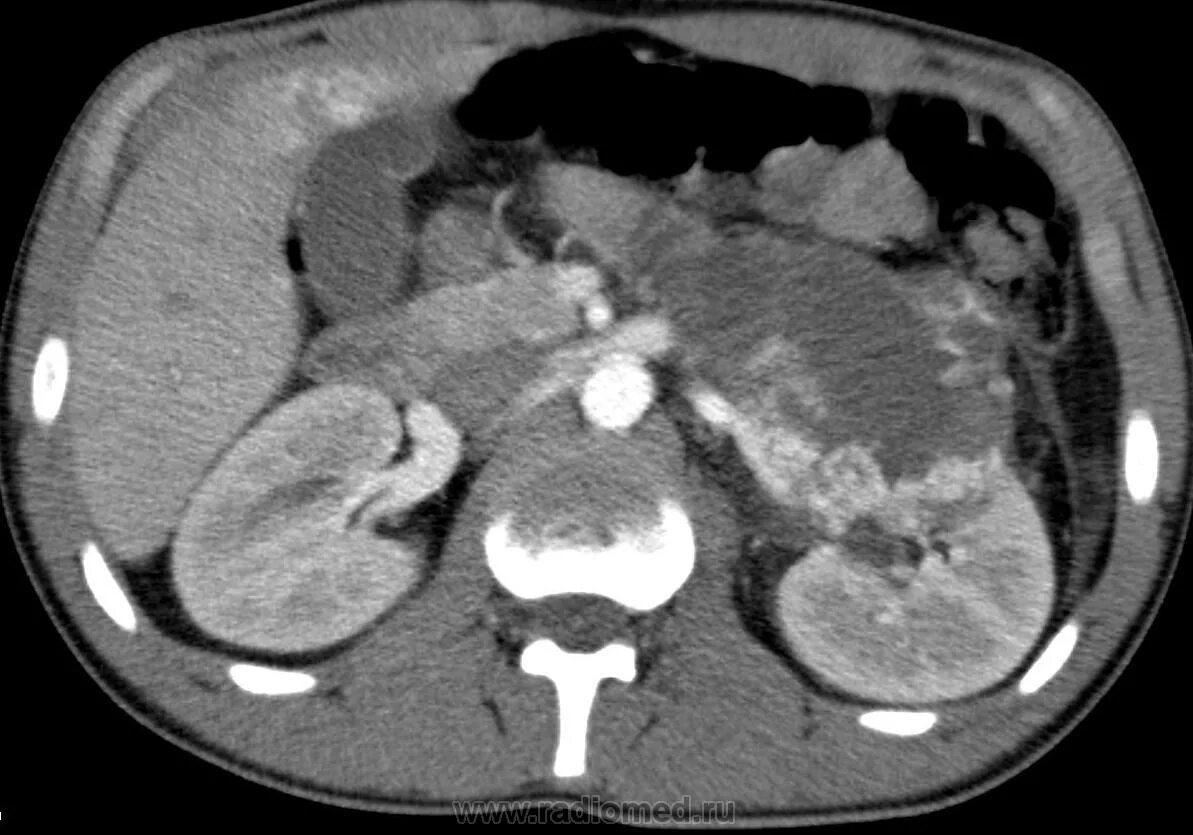

Метастазы при лимфоме